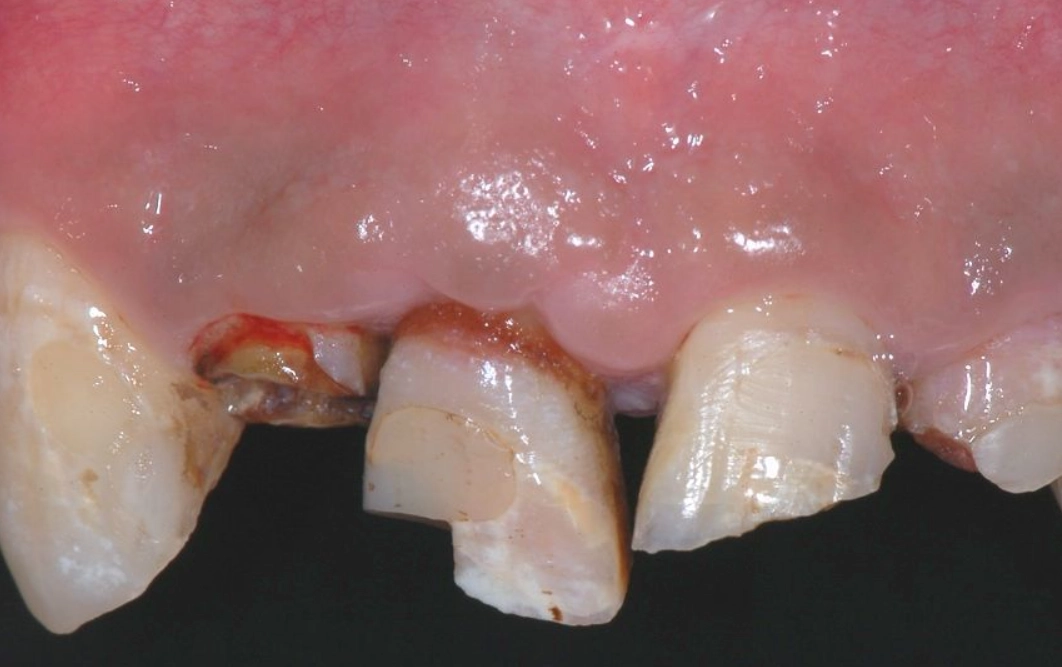

對,就是字面意思。排除生理原因永遠是第一步。夜間磨牙(學名:睡眠磨牙症)是導致牙齒斷裂的常見原因,而壓力正是磨牙的主要觸發因子之一。你可能完全沒意識到自己正在磨牙。

去看牙醫時,可以主動告知:「我最近夢到牙齒斷掉,有點擔心,可以請您幫我檢查是否有磨牙跡象或牙齒有隱裂嗎?」專業的牙醫能從琺瑯質磨損狀況判斷。如果真有磨牙問題,一副量身訂製的夜間牙套,既能保護你的牙齒,也從物理上中斷了「壓力→磨牙→夢到牙壞→更焦慮」的惡性循環。這是一個非常實際的自我照顧行動。